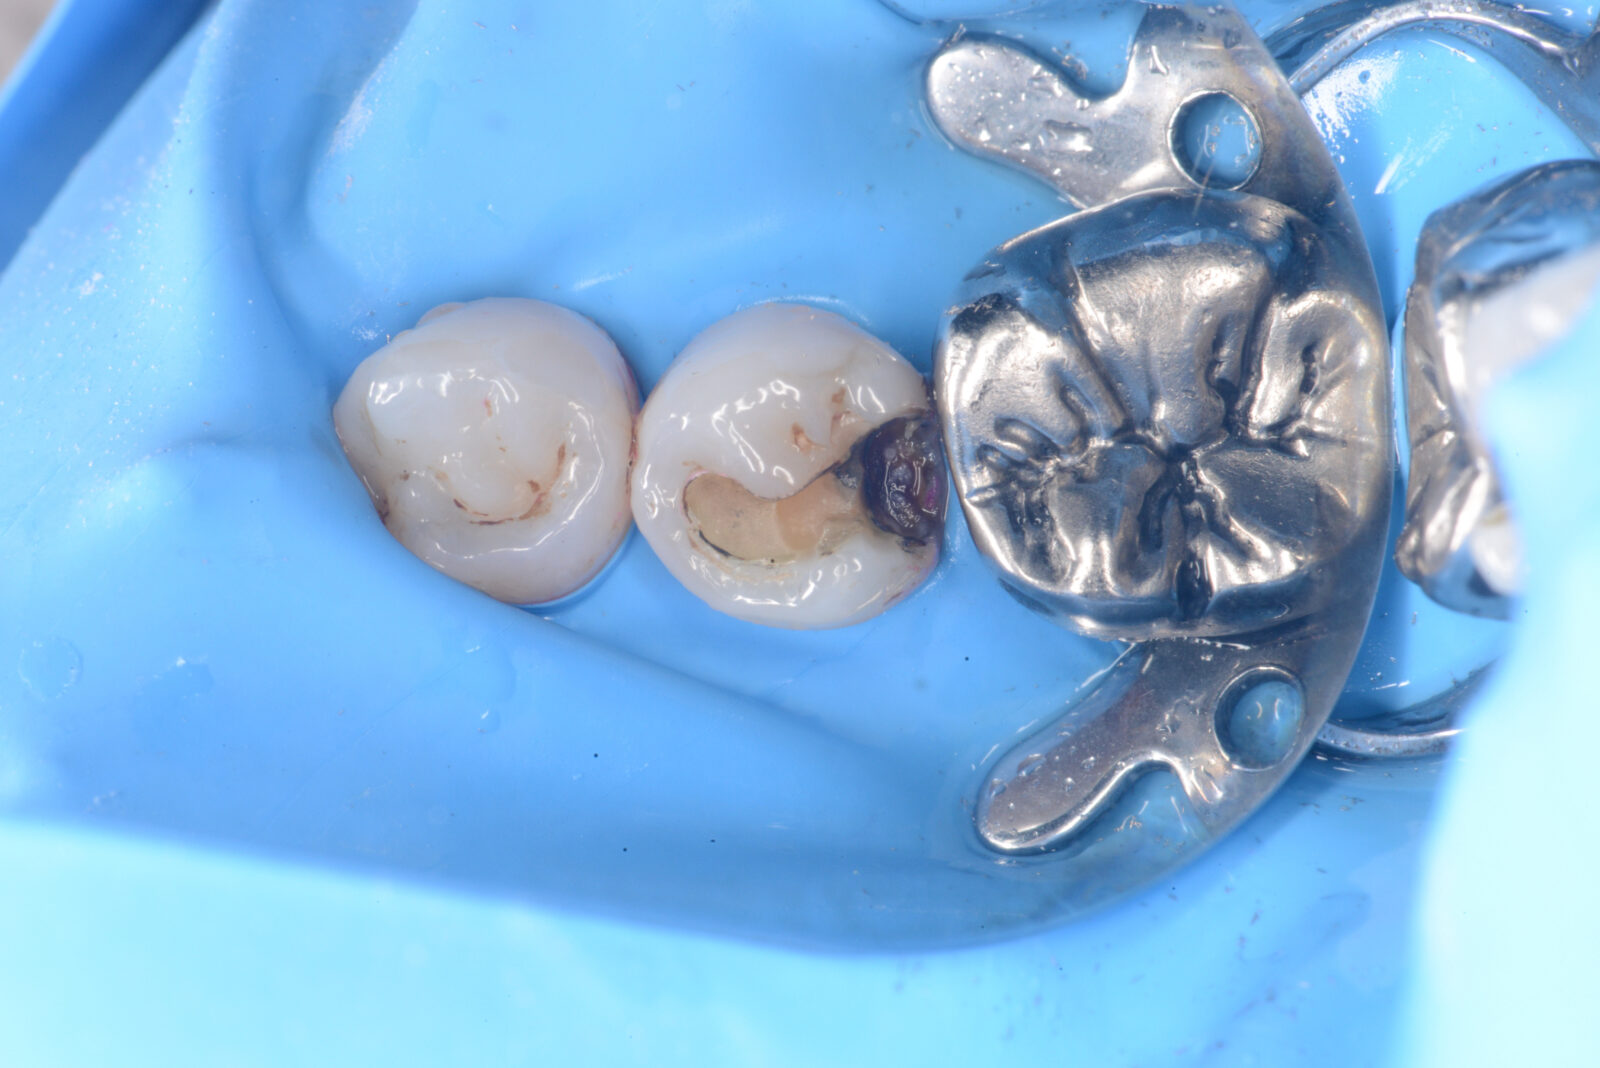

右下7ダイレクトボンディング

虫歯の治療希望で、右下の旧充填物と感染歯質の除去。 ラバーダム下で、プラークアウトと歯面処理を行い、接着操作とレジン充填を行った。 咬合調整はほぼなく研磨で終了。

2026.2.15